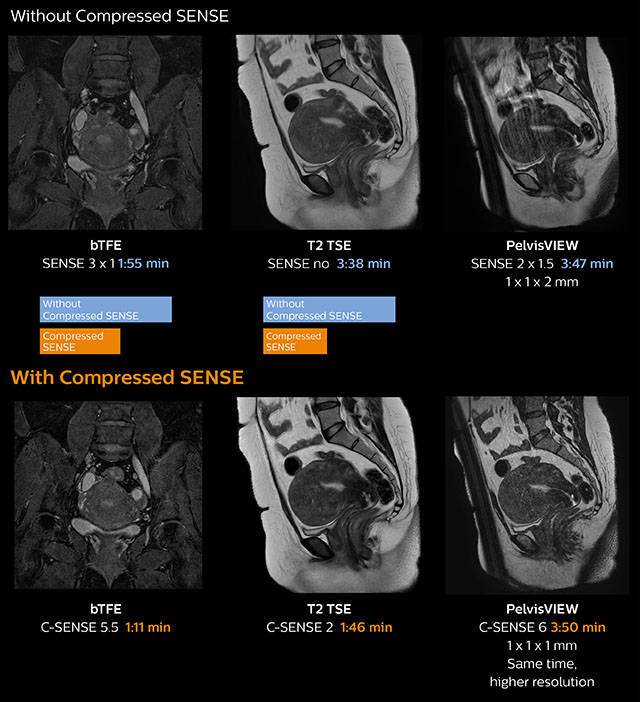

Pelvis with myoma – comparison w/wo Compressed SENSE

In this MRI exam of pelvis in a patient with myoma, Compressed SENSE is used to accelerate individual sequences and thus the entire examination on Ingenia 1.5T.

Compressed SENSE allowed for a decrease in scan time for the T2 TSE from 3:38 to 1:46 minutes. The Compressed SENSE images in this case show fewer motion artifacts than the images from the previous protocol with SENSE.

In 3D PelvisVIEW, the Compressed SENSE images have a higher and isotropic spatial resolution with a scan time similar to the SENSE sequence. The improved spatial resolution and better contrast in the myometrium of the uterus allowed radiologist Dr. Koyama to confidently diagnose the cancerous lesion in the uterus.

The use of Compressed SENSE accelerates scanning times and increases spatial resolution in 3D PelvisVIEW.